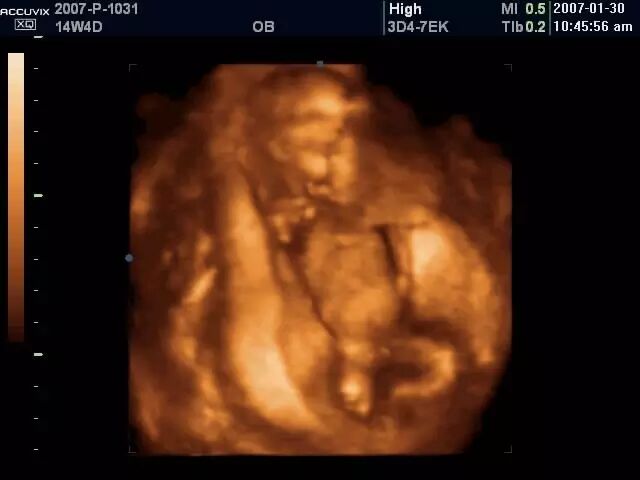

先天性马蹄内翻足的诊断大致可以分为两个阶段:I)产前诊断:最早可在妊娠 12-16 周即可通过三维或四维超声发现胎儿马蹄内翻足畸形的存在;II)出生后诊断:出生后通过临床检查可以明确诊断。